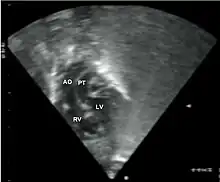

Echocardiogram: An echocardiogram is an ultrasound of the heart which accurately assesses the heart’s structure and function, and can show the specific features of TGA, if present. This imaging modality allows for the definitive diagnosis of TGA to be made. [8]

Echocardiography of a complex transposition with a ventricular septal defect and pulmonary stenosis.

Abbreviations: LV and RV=left and right ventricle, PT=pulmonary trunk, VSD=ventricular septal defect, PS=pulmonary stenosis.